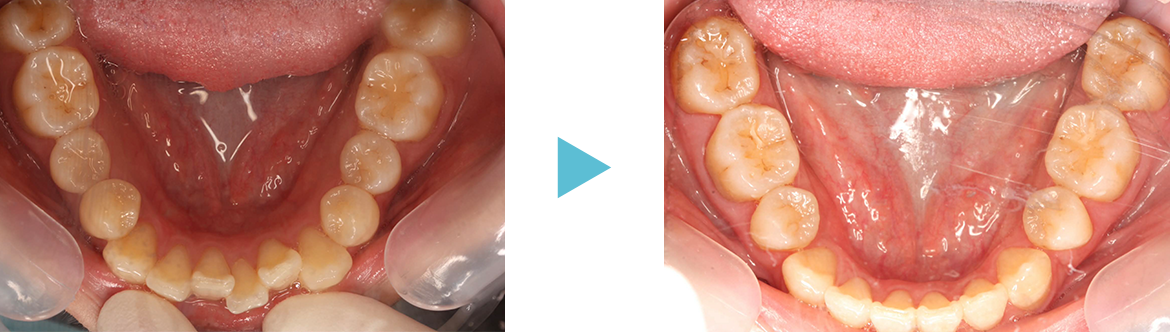

歯並びが混み合っている原因は歯の大きさに対して歯列(顎の大きさ)が小さいことが多いです。

硬いものをよく噛んでいれば顎が成長するのでしょうが、柔らかいものを食べている私たちは顎が小さくなっています。そこで歯列を大きくする拡大装置を使って歯列全体を大きくして永久歯が綺麗に並ぶように治療します。